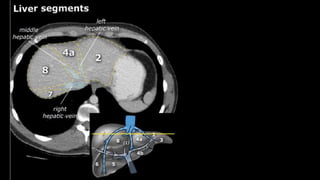

y is present, it is important to document its

location. This may be crucial to any surgical options. Using the

Couinaud classification, the liver is subdivided into eight individually

functioning segments. Each segment has its own afferent hepatic

artery and portal vein, and efferent hepatic vein and efferent bile

ducts

•Liver • A normalliver enhances homogeneously (irrespective of the scan phase). The liver receives about 80% of its blood through the portal vein (= nutrient-rich blood from the intestines). The remaining 20% is supplied by the hepatic artery. y is present, it is important to document its location. This may be crucial to any surgical options. Using the Couinaud classification, the liver is subdivided into eight individually functioning segments. Each segment has its own afferent hepatic artery and portal vein, and efferent hepatic vein and efferent bile ducts

Liver segments Radiopaedia.com1